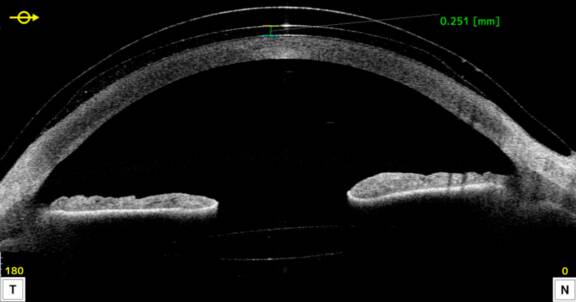

Mme G., 18 ans et sans antécédents particuliers hormis un terrain allergique, nous a été adressée en 2013 au CHRU de Lille pour un kératocône évolutif. L’examen initial retrouvait un astigmatisme important de 6 D lié à un kératocône de stade I. Son acuité visuelle était relativement préservée après une correction optique adaptée (10f/10 et 8/10), mais on notait une amélioration de l’acuité au trou sténopéique, ce qui présageait un gain en lentilles rigides.